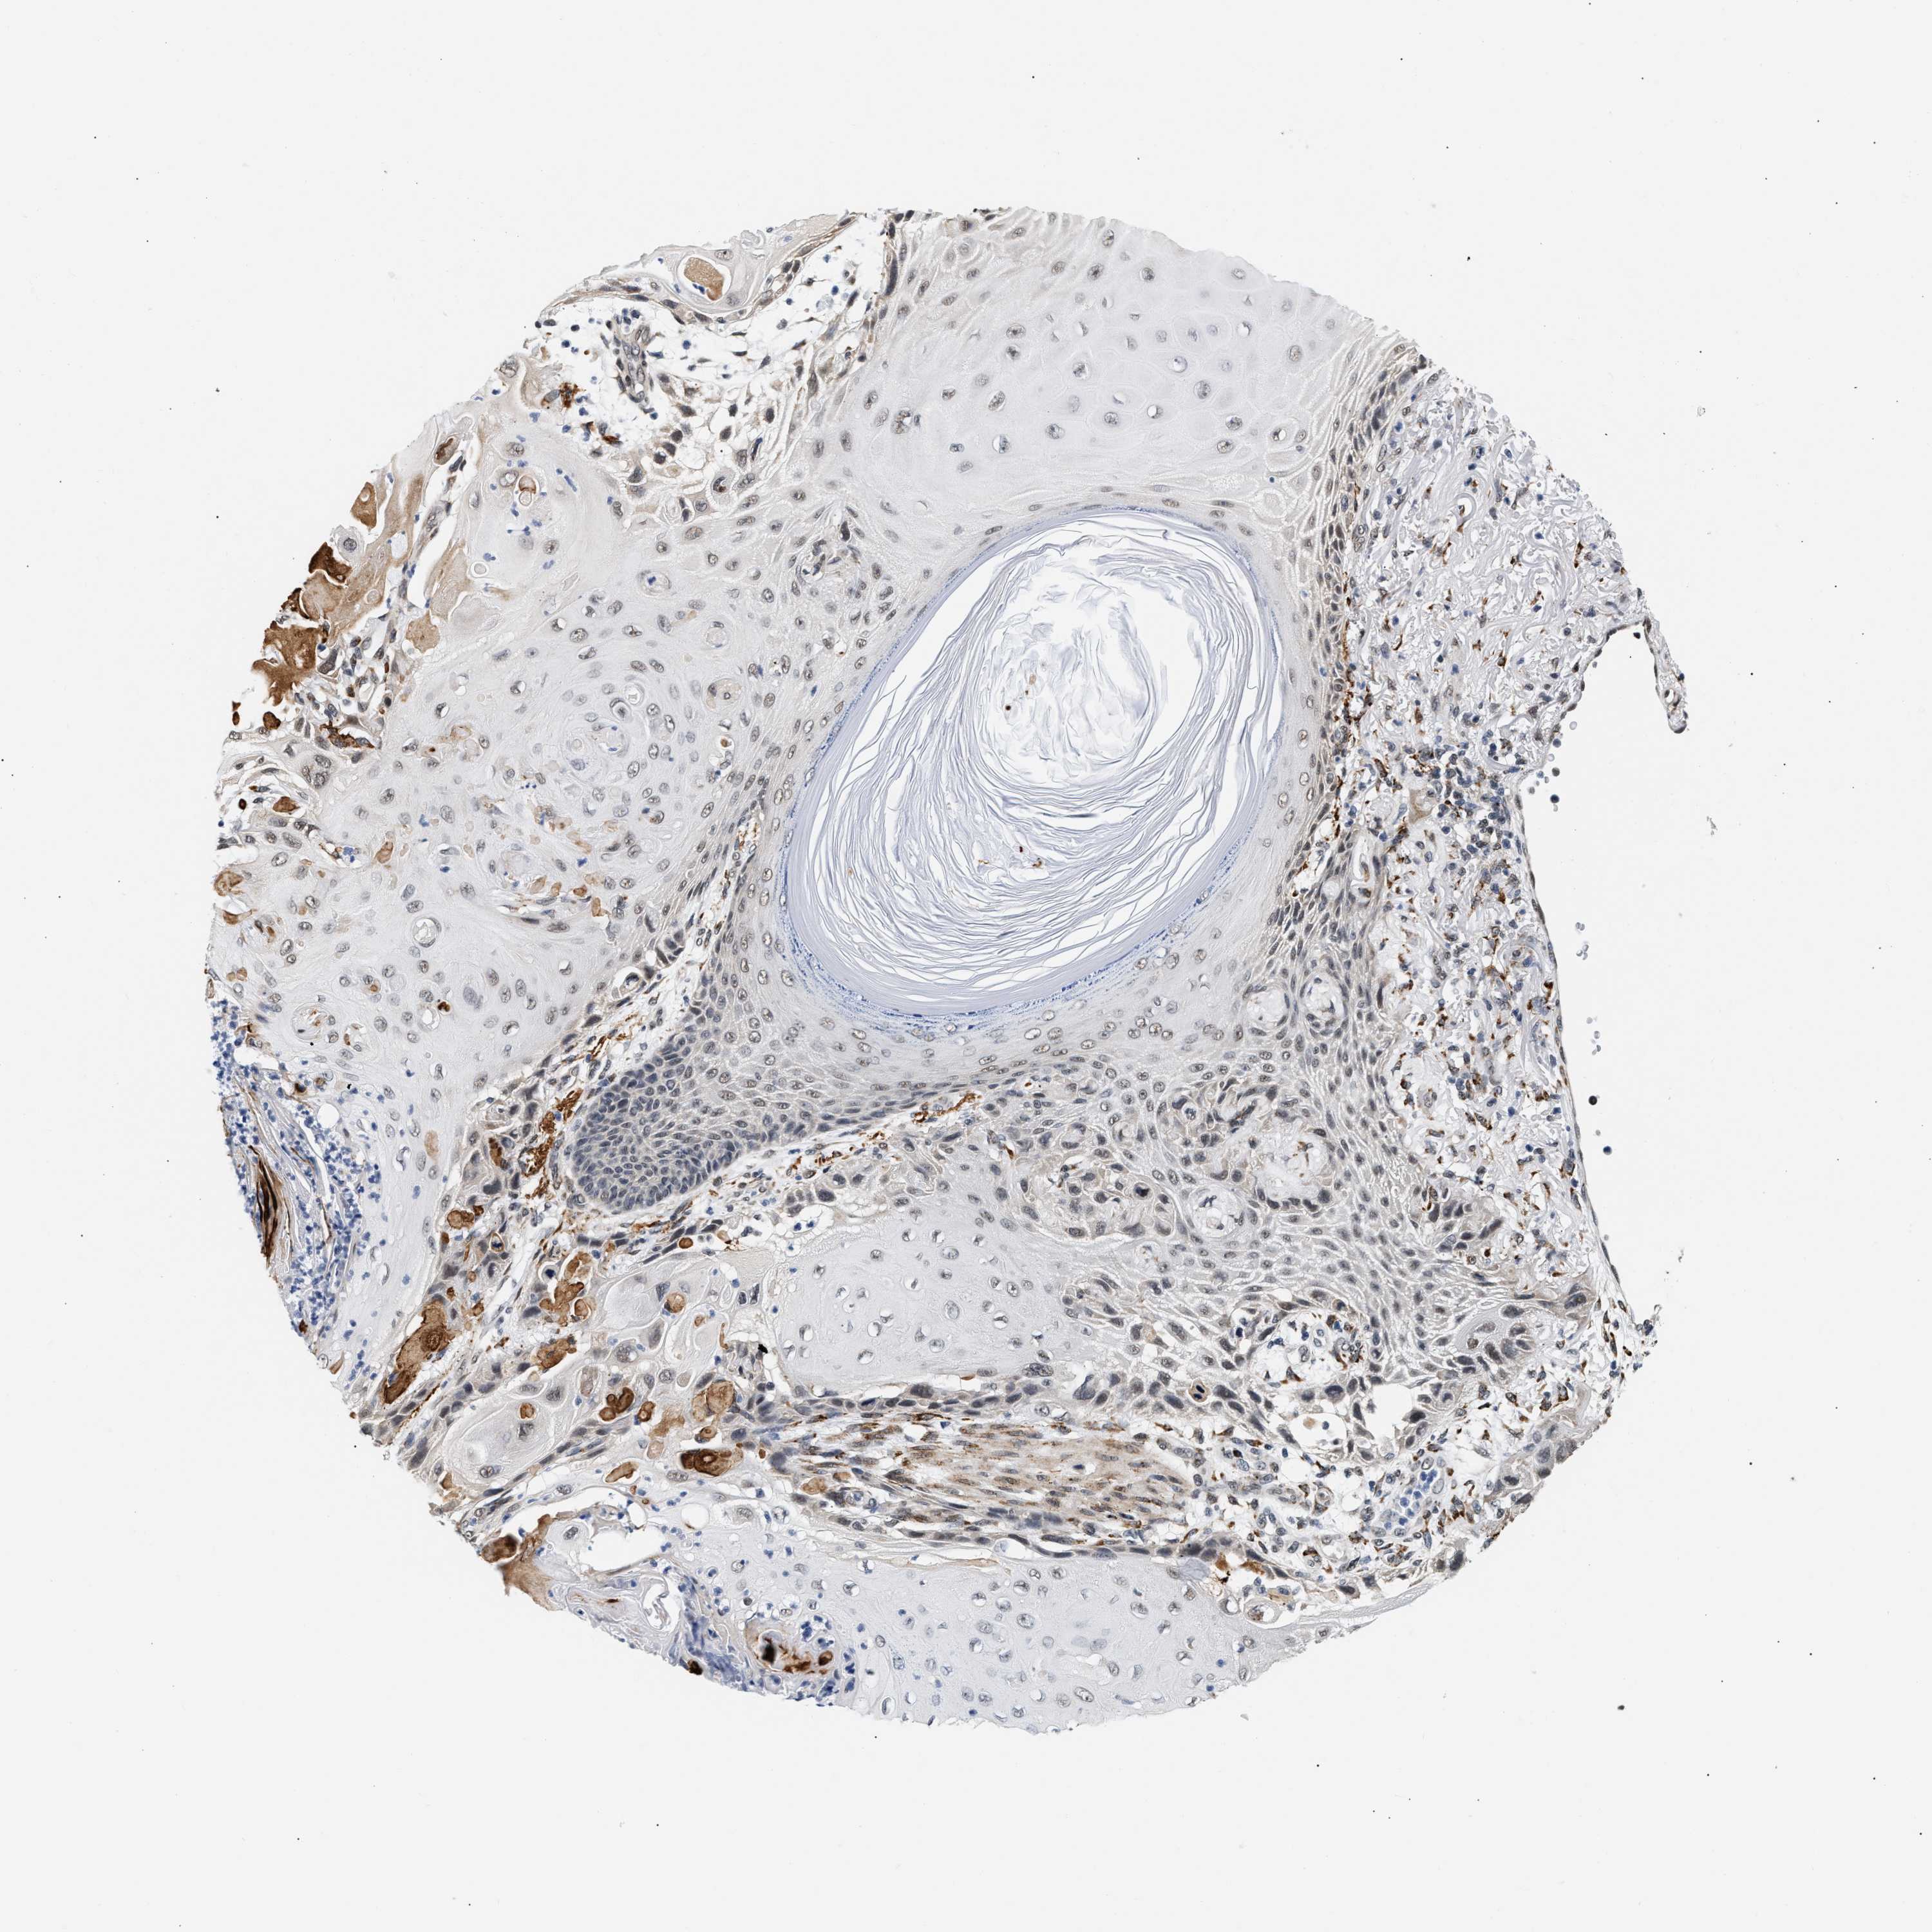

Basal cell and squamous cell cancer

SKIN CANCER - Protein expressioni

A mouse-over function shows sample information and annotation data. Click on an image to view it in a full screen mode. Samples can be filtered based on level of antibody staining by selecting one or several of the following categories: high, medium, low and not detected. The assay and annotation is described here.

Each image is clickable and will lead to virtual microscopy that enables deeper exploration of all samples and also displays staining intensity scores, fraction scores and subcellular localization as well as patient and tissue information for each sample.

Antibody HPA019687

Squamous cell carcinoma, metastatic, NOS

Squamous cell carcinoma, NOS